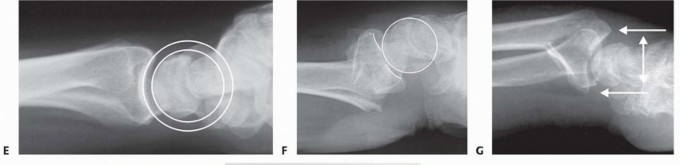

### FIG 5 • A. Carpal facet horizon (arrows). Used to differentiate between the volar and dorsal rim on the PA projection. B. Origin of carpal facet horizon. The carpal facet horizon is formed by that part of the articular surface that is parallel to the x-ray beam and depends on whether the articular surface is in volar or dorsal tilt. C. Normal teardrop angle. D. Depressed teardrop angle in this case is caused by axial instability of the volar rim. E. Normal articular congruency. F. Abnormal articular congruency, indicating disruption across the volar and dorsal surfaces of the lunate facet. G. AP interval is the point-to-point distance between the corners of the dorsal and volar rim. H. DRUJ interval. I. Normal lateral carpal alignment. J. Dorsal subluxation of the carpus. Congruency of the articular surface ( FIG 5E,F). The subchondral outline of the articular surface of the distal radius is normally both congruent and concentric with the subchondral outline of the base of the lunate; a uniform joint interval should be present between the radius and lunate along the entire articular surface. When the joint interval between these articular surfaces is not uniform, discontinuity and disruption of the lunate facet has occurred. Anteroposterior (AP) distance (normal: females 18 ± 1 mm, males 20 ± 1 mm; FIG 5G). The AP distance is the point-to-point distance from the dorsal to palmar rim of the lunate facet. It is best evaluated on the 10- degree lateral view. Widening of the AP distance implies discontinuity of the volar and dorsal portion of the lunate facet. 80 DRUJ interval ( FIG 5H). The DRUJ interval measures the degree of apposition between the head of the ulna and the sigmoid notch (normal: 2 mm or less). This parameter is best measured with the forearm in neutral rotation. Significant widening of the DRUJ interval implies disruption of the DRUJ capsule and TFCC. Coronal malalignment of the distal radial fragment is often suggested by widening of the DRUJ interval. Lateral carpal alignment ( FIG 5I,J). On the 10-degree lateral view and with the wrist in neutral position, the rotational center of the capitate normally aligns with a line extended from the volar surface of the radial shaft. Dorsal rotation of the volar rim results in a dorsal shift of lateral carpal alignment as the carpus subluxes dorsally. This may place the flexor tendons at a mechanical disadvantage, affecting grip strength. In addition to injury films, reassessing radiographs after reduction can be very helpful in determining the personality and specific components of a particular fracture. Computed tomography (CT) scans allow higher resolution and definition of fracture characteristics, particularly for highly comminuted fractures. Preferably, an attempt at closed reduction before obtaining a CT scan will help limit distortion of the image. CT scans are particularly helpful for visualizing intra-articular fragments as well as DRUJ disruption and incongruity of the sigmoid notch. Clinical evaluation of the carpus, interosseous membrane, and elbow, combined with radiographic studies when needed, should be included to identify the presence of other injuries that may affect the decision for a particular treatment. ## SURGICAL MANAGEMENT